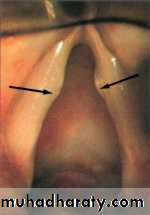

Depressing the tongue may show swollen, red cherry epiglottis but no attempt should be made to examine the larynx as this may end in fatal total obstruction. It is better done in operation theature where facilities for intubation or tracheostomy are available.

Steeple sign (Croup) Thumb sign (Epiglottitis)